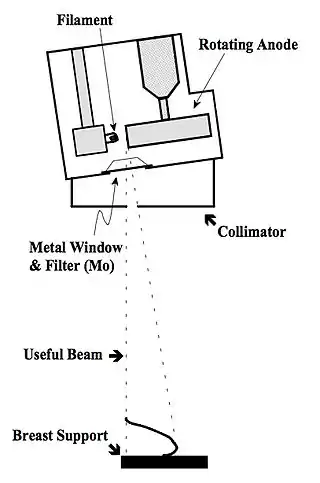

- Mammography XRTs are generally constructed with a metal envelope, instead of the usual glass, with a thin beryllium (Be) exit port. This design has the advantage of suppressing extra-focal radiation. In addition, the tube can be constructed so that the anode-cathode axis is offset to achieve the small focal spot size - see Figure 7.23.

- Furthermore, it has been found that the focal spot should be located on a line, perpendicular to the image receptor, which contains the chest wall margin. Equally importantly, the collimator should also be adjusted to ensure that the X-ray beam intercepts the image receptor on that margin.